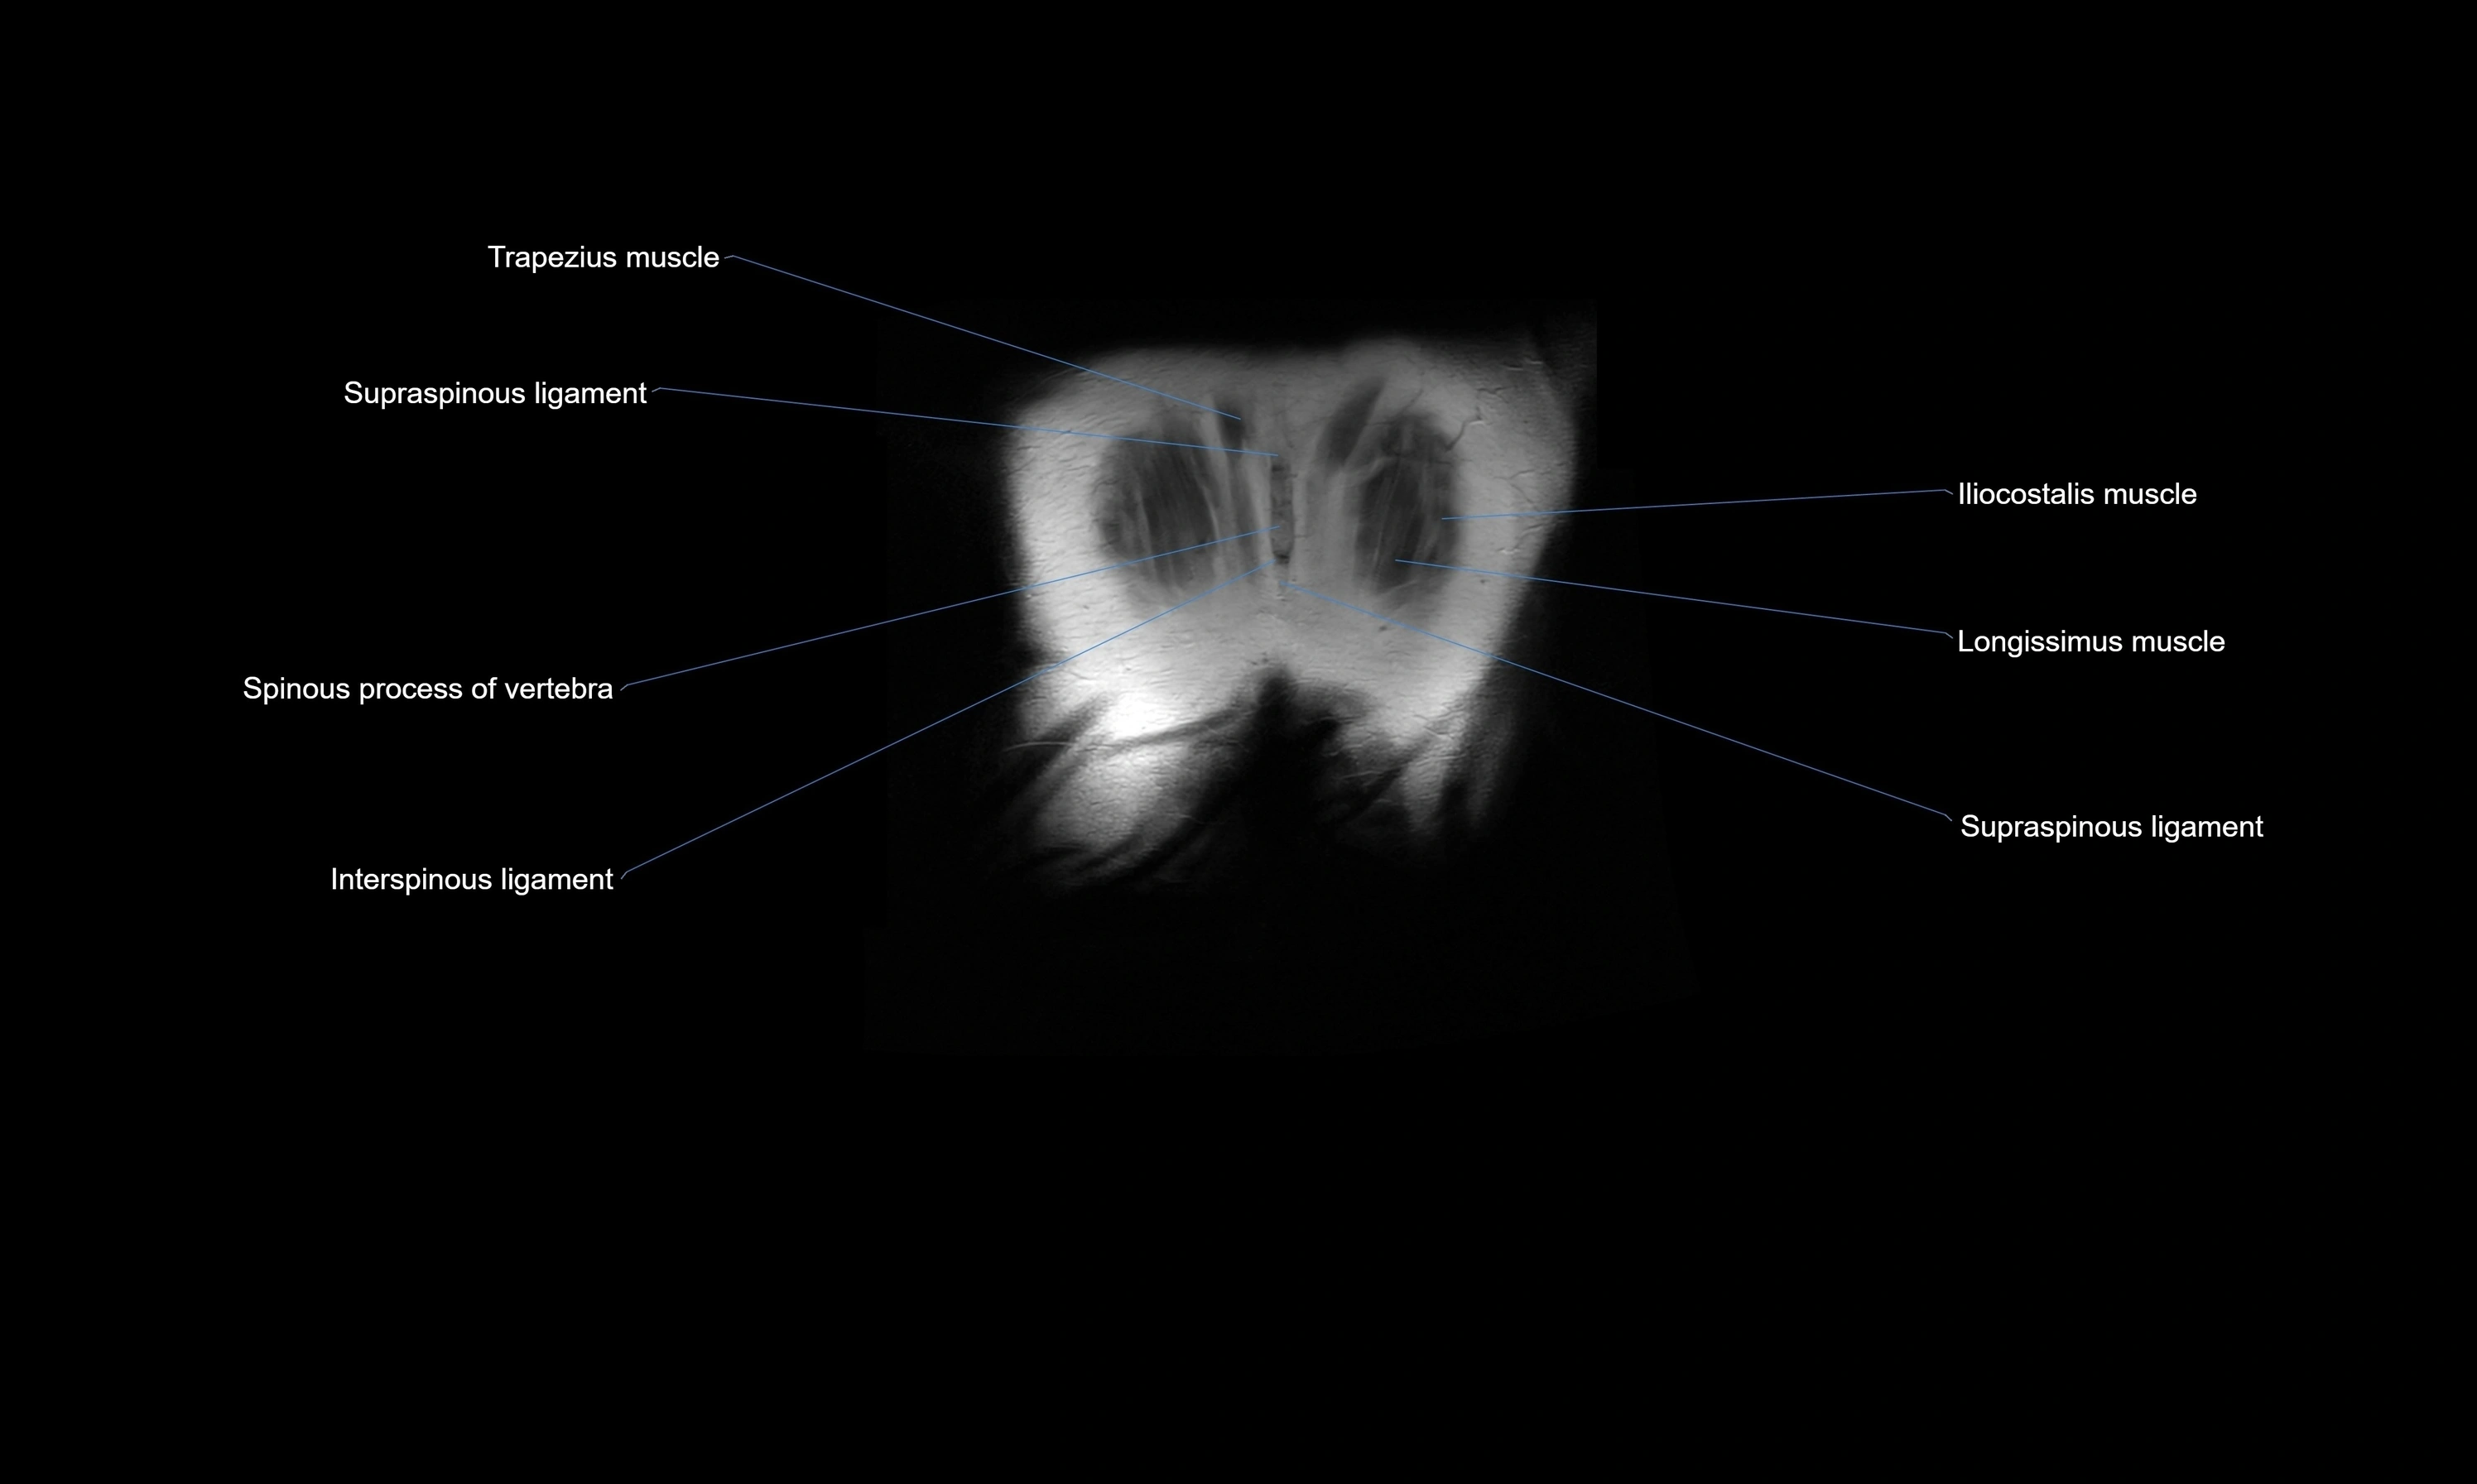

- Spinous process of vertebra

- Supraspinous ligament

- Interspinous ligament